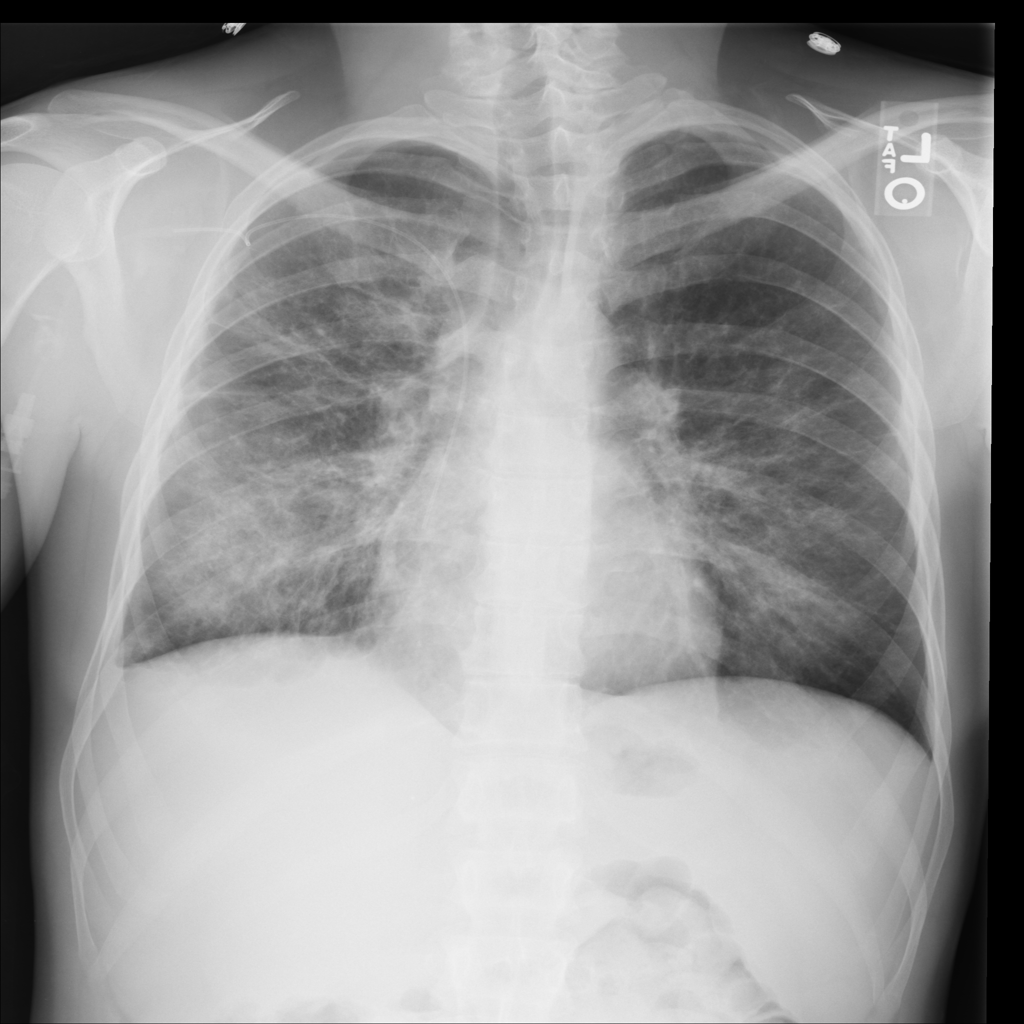

Showing up to 90 reference images for Pneumonia.

PAT-C0E5 · IMG-015Pneumonia

PAT-C0E5 · IMG-015

AP